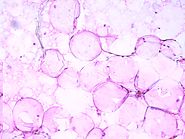

Learn about adipofilling which revolutionises lipofilling. The innovative procedures in which this method is used are illustrated in the section Adipofilling of the CRPUB.ORG Medical Video Journal, ISSN 1971-8152. Adipofilling is a new method of preparing and transferring adipose tissue. Adipofilling consists of grafting a cell suspension of adipocytes and stromal cells.

Adipofilling is a biological filler of adipose cells and connective material. Learn the innovative methods in which Adipofilling is used to grafting adipose tissue.